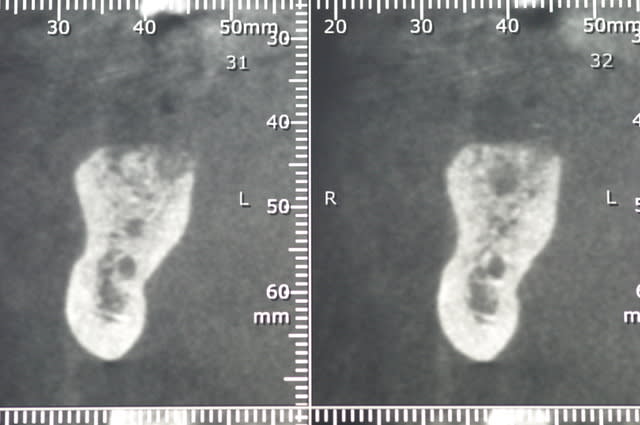

ci joint les photos des coupes scanner d'un patient à qui j'ai proposé de poser un implant afin de remplacer la 36. sur les coupes, on vois nettement le dédoublement du NAI.

Après discussion avec le radiologue qui ni avait pas fait allusion dans son compte rendu, celui-ci me dit que le canal le canal ne contient que quelques filet nerveux (je ne sais pas comment il peut voir cela..) et que je peux passer au travers sans problèmes.

je voulais savoir si certains d'entre vous avaient déjà traversé des branches accessoires du NAI aussi volumineuse radiologiquement.